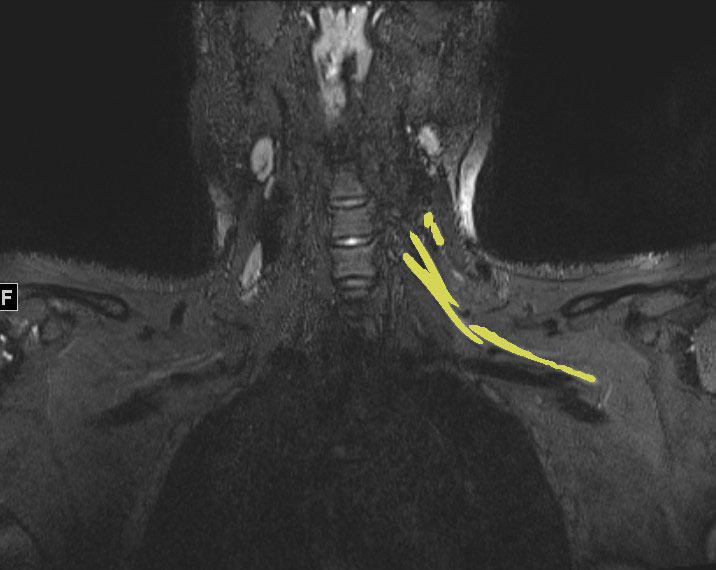

Spinal nerve issues often appear quite well on MRI. When discs bulge or herniate, they frequently press against nerve roots, creating visible compression. Spinal stenosis – where the spinal canal narrows – also shows up clearly as the space around nerves becomes cramped.

Peripheral nerves in your arms and legs can also be seen on MRI, especially when they’re significantly swollen or compressed. Carpal tunnel syndrome sometimes appears on specialized wrist MRI scans, showing the median nerve getting squeezed in the narrow tunnel at your wrist.